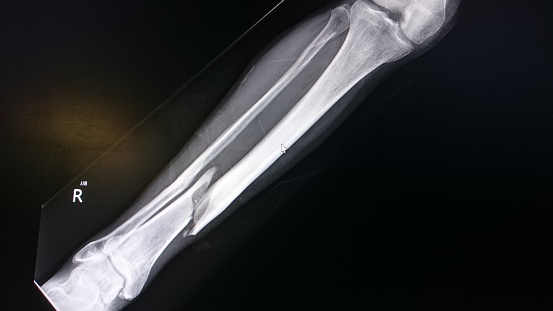

Las fracturas ocurren por accidentes, caídas o lesiones deportivas. Estas son rupturas, generalmente en un hueso. Si el hueso roto rompe la piel, se denomina fractura abierta o compuesta. Entérate de los síntomas y tratamientos necesarios aquí ow.ly/aGbX50BlY82